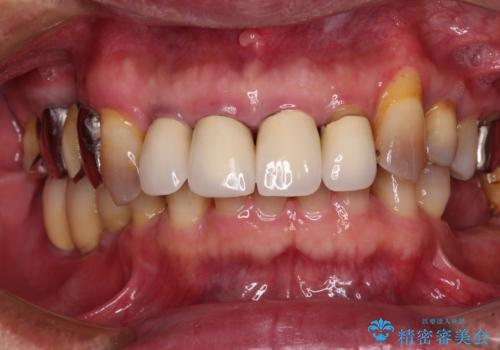

- 奥歯の欠損部へのインプラント治療を希望して来院された患者様です。

インプラント治療に当たり、手前の銀歯2本の審美回復も希望されたため、3歯のオールセラミッククラウンによる補綴治療を行うこととしました。

通常、奥歯を抜歯した状態で長年放置すると、咬み合う歯が伸びてきて、咬み合わせが乱れてしまうことが多いです。そのような場合には、部分的な矯正治療などが必要となるのですが、こちらの患者様は幸運なことに咬み合わせが乱れていなかったため、インプラント埋入から速やかに補綴治療を行うことができました。